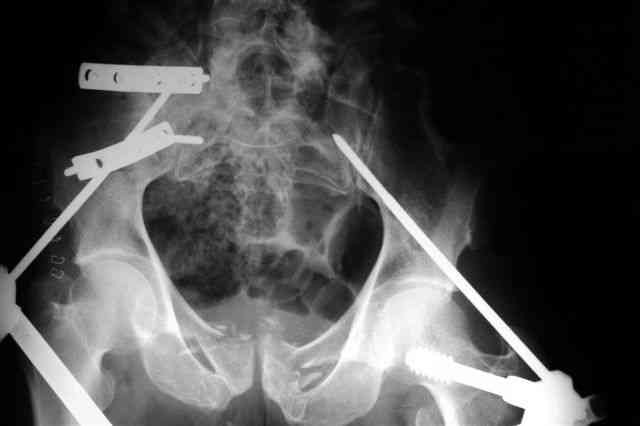

В приложении послеоперационные картинки.